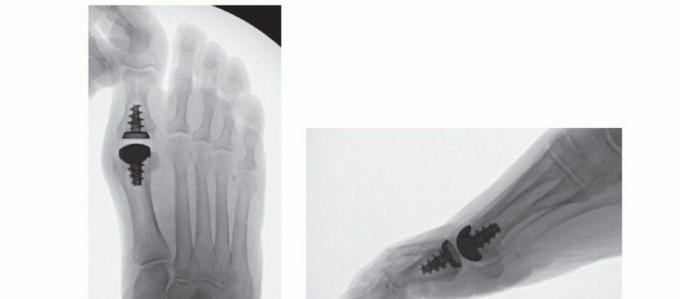

Given the lack of significant rates of loosening seen with this implant, recent FDA approval has been obtained for a novel total toe arthroplasty design (Arthrosurface ToeMotion Total Toe Arthroplasty) using the same tapered screw fixation method within proximal phalanx (FIG 9). A proximal phalangeal component with polyethylene insert was created as a complement to the metatarsal HemiCAP DF implant in an effort to address progressive arthritic changes of the proximal phalangeal articular surface. When significant involvement of both sides of the joint are seen at the time of the index procedure, use of the ToeMotion total toe arthroplasty design would be more appropriate than a hemiarthroplasty alone with the desired goal of providing a more predictable procedure for pain relief.

FIG 9 • A. Arthrosurface ToeMotion total toe arthroplasty implant. Inlay arthroplasty using taper screw-based fixation and modular polyethylene insert. (continued)

FIG 9 • (continued) B-E. Radiographs of ToeMotion total toe arthroplasty.